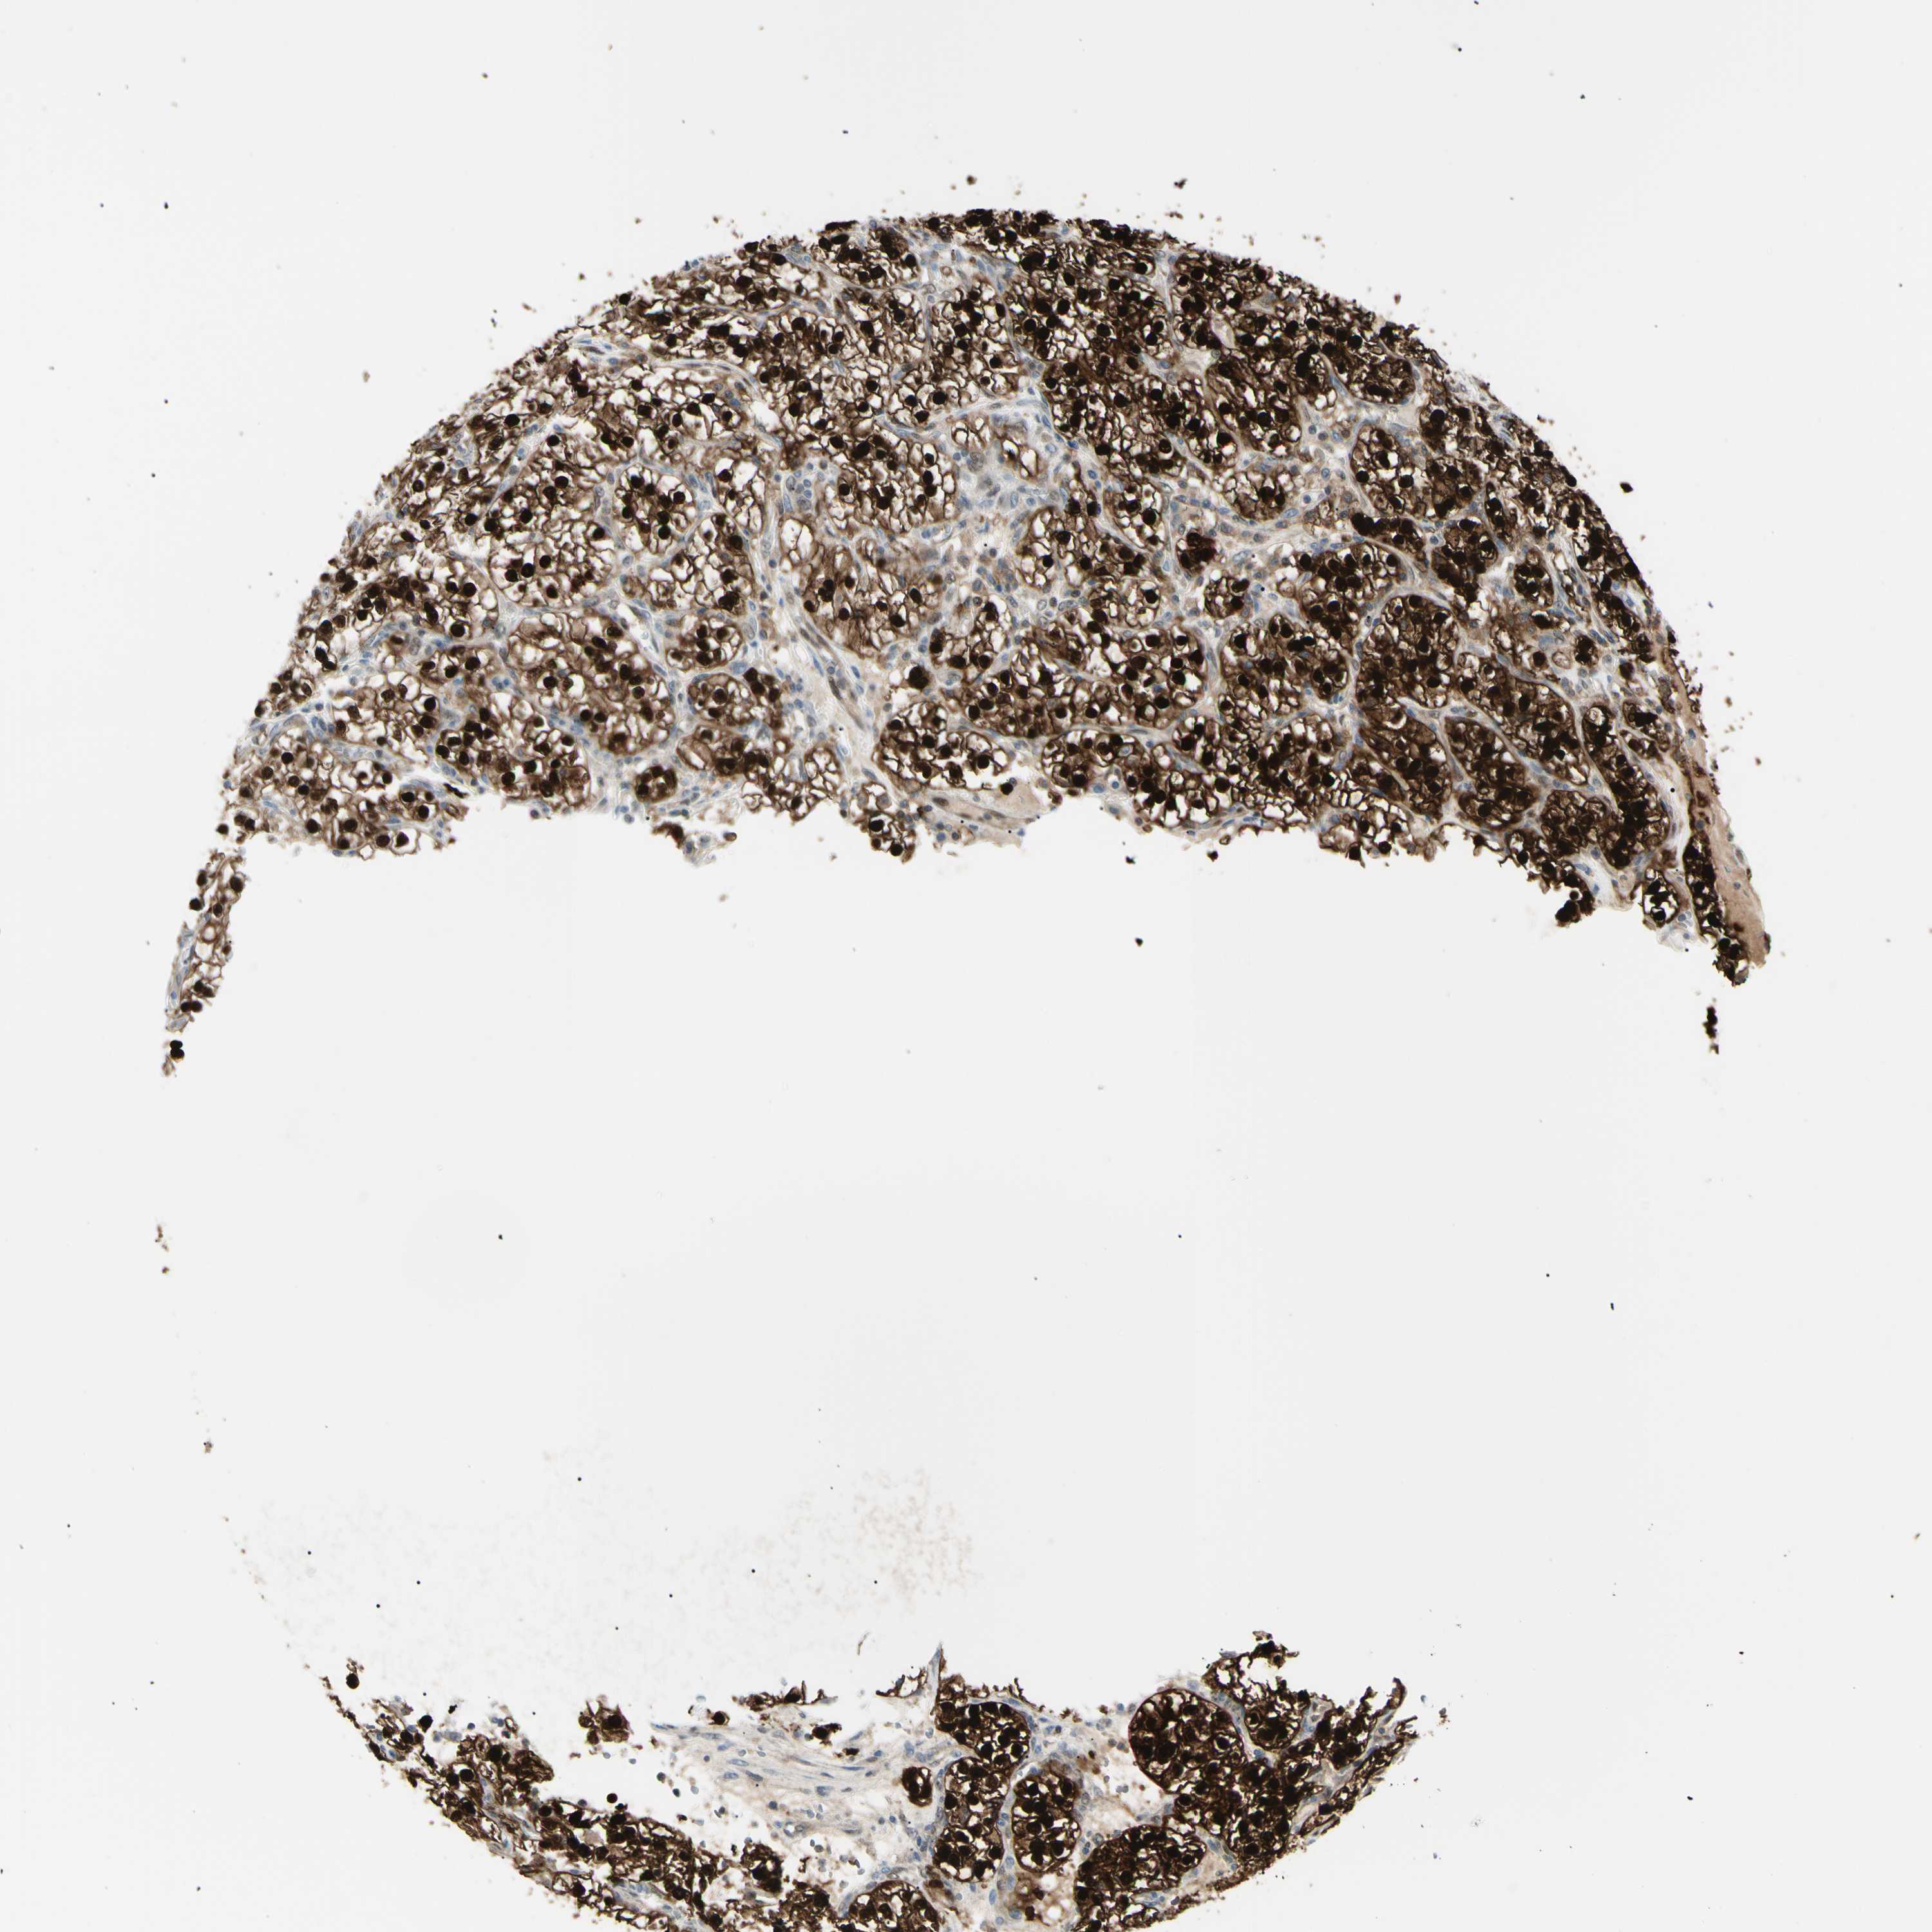

CANCER RENAL CANCER Show tissue menu

KICH TCGA KIRC TCGA KIRC VALIDATION KIRP TCGA PROTEIN RCC CPTAC PROTEIN EXPRESSION